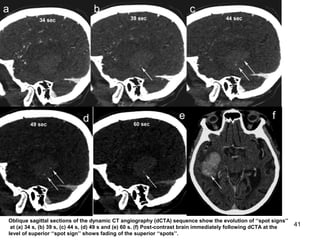

Oblique sagittal sections of the dynamic CT angiography (dCTA) sequence show the evolution of ‘‘spot signs’’

at (a) 34 s, (b) 39 s, (c) 44 s, (d) 49 s and (e) 60 s. (f) Post-contrast brain immediately following dCTA at the

level of superior ‘‘spot sign’’ shows fading of the superior ‘‘spots’’.